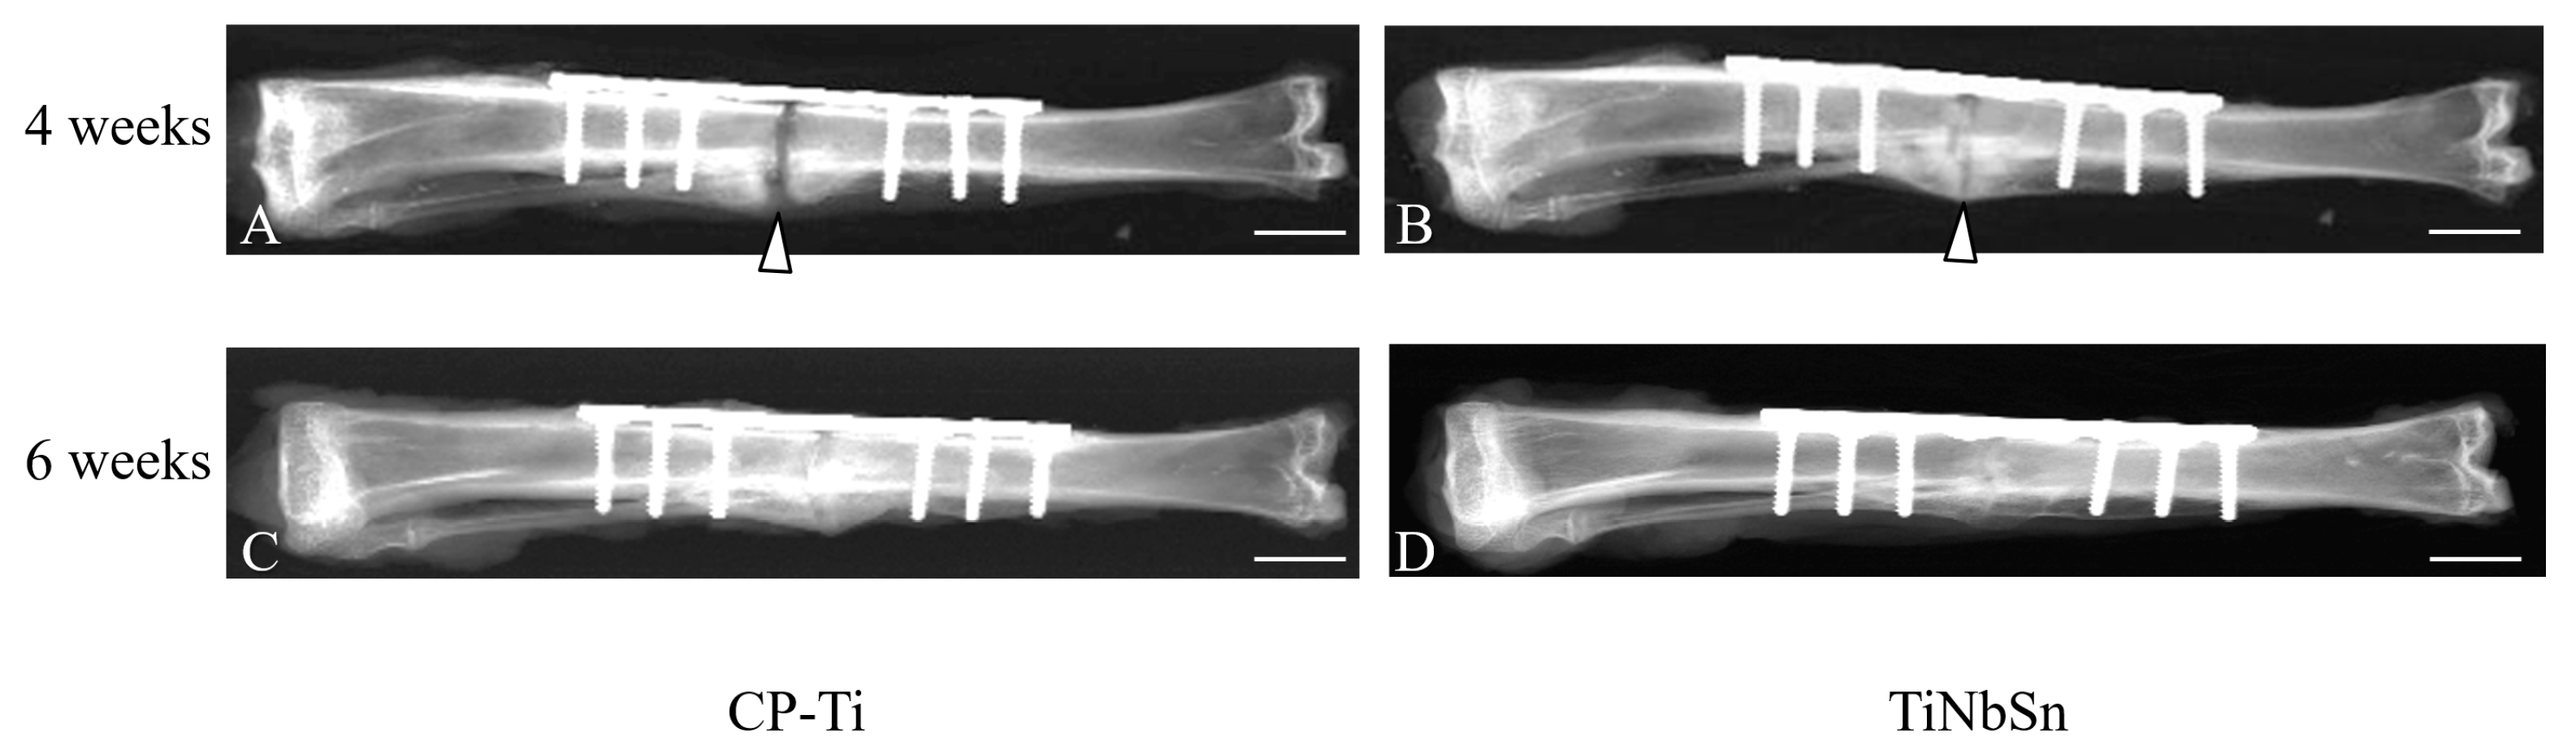

Results from studies on rabbit and murine tibia fractures treated with intramedullary nails indicate that nails fabricated from the TiNbSn alloy are more efficacious in facilitating osteosynthesis compared to materials possessing higher Young’s moduli [55,56,57]. The effect of the TiNbSn alloy compared with CP-Ti in promoting osteosynthesis in a rabbit tibial osteotomy model is presented in Figure 2 [58].

Figure 2.

Radiographs after osteotomy in rabbit tibia. (A) Commercially pure titanium (CP-Ti), 4 weeks after osteotomy; (B) TiNbSn alloy, 4 weeks after osteotomy; (C) CP-Ti, 6 weeks after osteotomy; (D) TiNbSn alloy, 6 weeks after osteotomy. Arrowheads indicate fracture callus. The scale bar indicates 10 mm. Reproduced from ref. [58] with permission [58].

The results demonstrated that in the TiNbSn alloy group, the bone healing process was linked to heightened callus formation, improved structure of newly formed bone, greater bone strength in the early phase, and enhanced bone strength and stiffness during the late phase of bone healing. Adequate IFM and controlled axial motion are provided by elastic intramedullary nails composed of a TiNbSn alloy with a low Young’s modulus, and these motions may contribute to better bone healing and superior mechanical properties. Additionally, the impact of the fracture plate’s low Young’s modulus on osteosynthesis was examined. Radiological, histological, and mechanical evaluations have suggested the outstanding effectiveness of the TiNbSn alloy on bone repair compared to both CP-Ti and Ti6Al4V alloy [11,58]. The TiNbSn alloy is a titanium alloy with a low Young’s modulus and could be equipped with a locking mechanism [58]. Utilizing an implant fabricated from a material with a lower Young’s modulus, which facilitates more effective load sharing with the bone compared to an implant made of Ti6Al4V, could confer advantages for bone healing and potentially diminish the risk of stress shielding. Specifically, a TiNbSn alloy plate, characterized by its low Young’s modulus, demonstrated superior new bone formation and produced a stiffer callus at the osteotomy site, particularly during the initial phases of the healing process, in comparison to plates made from Ti6Al4V alloy and CP-Ti [11,58]. The TiNbSn alloy group exhibited a more robust formation of intramedullary callus with a well-developed bone structure than the Ti6Al4V alloy and CP-Ti groups. At the osteotomy site, the TiNbSn alloy group demonstrated a more advanced formation of mature bone, accompanied by improved orientation of the bone structure (Figure 3).